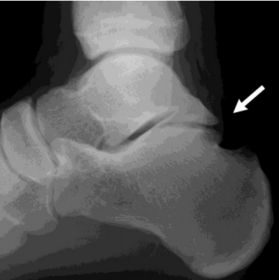

What disease is this? What does the arrow indicate? | Rheumatoid arthritis. Arrow = Bone erosion secondary to inflammation of retrocalcaneal bursa. |